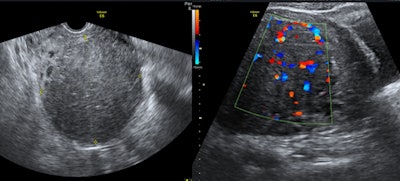

The minimally invasive interventional radiology procedure of uterine fibroid embolization (UFE) has a lower complication rate than myomectomy. It may be performed if a woman has a single fibroid, many fibroids, or large-sized fibroids and a gynecologist cannot rule out a hysterectomy during myomectomy, myomectomy is unsuccessful, or when fibroids recur after myomectomy. The procedure may also be performed for women who want to avoid surgical removal for culture reasons, surgically high-risk women with fibroids, women of any age with fibroids who want to preserve their uterus and avoid the psychological trauma of hysterectomy, and, more important, in unmarried virgin women with fibroids.

Uterine fibroid embolization blocks blood supply to treat painful uterine fibroids, and the procedure has a comparable fertility rate to myomectomy for women who want to conceive, according to what is thought to be the first study on the subject in the Middle East. The study was conducted by our group at Al Ain Hospital and presented ahead of print at the 2016 Arab Health Conference in Dubai, United Arab Emirates, in January and also presented at the Abu Dhabi annual gynecology conference in October 2015 and the Cleveland Clinic Abu Dhabi radiology conference in November 2015.

In this study, most women opted for UFE as a fertility treatment after failure of myomectomy or in vitro fertilization, or because hysterectomy was the only suggested option. Of the 210 patients who received UFE treatment, 35 women younger than the age of 40 wanted to conceive and had been unable.